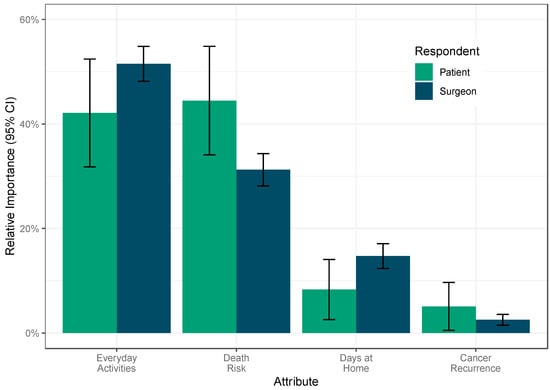

The Design of a Patient-Centered Hierarchal Composite Outcome for a Multi-Center Randomized Controlled Trial in Metastatic Bone Disease

Curr. Oncol. 2025, 32(6), 318; https://doi.org/10.3390/curroncol32060318 - 30 May 2025

The proximal femur represents the most frequent site in the appendicular skeleton for metastatic bone disease (MBD) to occur, with a high risk for pathologic fracture. While surgical stabilization is typically used to manage fractures, reconstruction approaches are gaining popularity due to improved survival. Previous studies have focused on clinical outcomes, but patient-centered outcomes remain underexplored. This study aims to develop a patient-centered primary outcome for the Proximal FEmur Reconstruction or Internal Fixation fOR Metastases (PERFORM) Randomized Controlled Trial, employing a mixed-methods approach. First, a focus group with advanced cancer patients and caregivers identified relevant outcomes. Next, a discrete choice experiment (DCE) assessed the importance of these outcomes among stakeholders, including surgeons, patients and caregivers. The most important components for the primary outcome were identified: mortality within twelve months, physical function assessed at four months using the PROMIS® Global Physical Function score, and the number of days at home within twelve months. The DCE further confirmed that survival and physical function were most prioritized. The PERFORM trial’s primary outcome, developed through extensive stakeholder engagement, will guide the evaluation of surgical approaches for MBD of the proximal femur and has the potential to influence patient-centered practice.